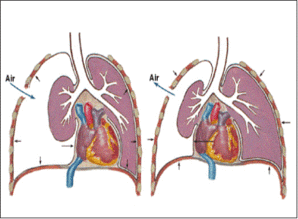

根據(jù)發(fā)病原因氣胸可分為以下幾種類型: 1、創(chuàng)傷后氣胸:胸部被銳器刺傷后引起; 2、原發(fā)性氣胸:沒有肺部明顯病變的健康者所發(fā)生的氣胸,多見于20-40歲的青壯年,男性多見; 3、繼發(fā)性氣胸:繼發(fā)于肺部各種疾病基礎(chǔ)上發(fā)生的氣胸,如慢性支氣管炎、肺氣腫、肺結(jié)核、肺癌等。 根據(jù)病理結(jié)構(gòu)氣胸又分為以下類型: 1、閉合型氣胸(單純性氣胸):肺受胸膜腔內(nèi)氣體壓迫而萎縮,破口閉合不再漏氣; 2、開放性氣胸:實際上是支氣管胸膜瘺,破口始終開放,抽氣后壓力不變,此型氣胸較少見,在呼吸周期中產(chǎn)生縱隔擺動,嚴(yán)重影響呼吸循環(huán)生理; 3、張力性氣胸(高壓性氣胸):破口形成單向活瓣,吸氣時活瓣開放,空氣進(jìn)入肺內(nèi)時活瓣關(guān)閉,空氣不能逸出,胸膜腔內(nèi)壓力逐漸升高,抽氣后可短時降低,不久再度升高,此型為內(nèi)科急癥,可引起呼吸循環(huán)功能嚴(yán)重障礙,甚至產(chǎn)生缺氧和休克。

原發(fā)性氣胸通常是由于先天性肺組織發(fā)育不全,胸膜下存在著的肺小皰或肺大皰破壁后引起,病變常位于肺尖部;繼發(fā)性氣胸是由于原有的肺臟病變,形成胸膜下的肺大皰破裂或者是由于病變本身直接損傷胸膜所致。 自發(fā)性氣胸多為單側(cè),雙側(cè)同時存在僅占10%左右,繼發(fā)性氣胸則雙側(cè)同時存在的機(jī)率極大,患者氣胸后常有突發(fā)胸痛,為尖銳持續(xù)性刺痛或刀割痛。

吸氣加重,多在前胸、腋下部,可放射到肩、背、上腹部,隨之出現(xiàn)呼吸困難,嚴(yán)重程度與氣胸發(fā)生的快慢、類型、肺萎縮程度和基礎(chǔ)肺功能有密切關(guān)系,單側(cè)閉合型氣胸,尤其肺功能正常的青年人可無明顯呼吸困難,甚至肺壓縮80-90%或僅在活動、上樓時稍感氣短,而張力性氣胸或原有阻塞性肺氣腫的老人可有明顯呼吸困難,即使肺壓縮僅20-30%時也有氣急。刺激性干咳是由于氣體刺激胸膜產(chǎn)生,多不嚴(yán)重,無痰或偶有少量血絲痰,可能來自肺破裂部位。